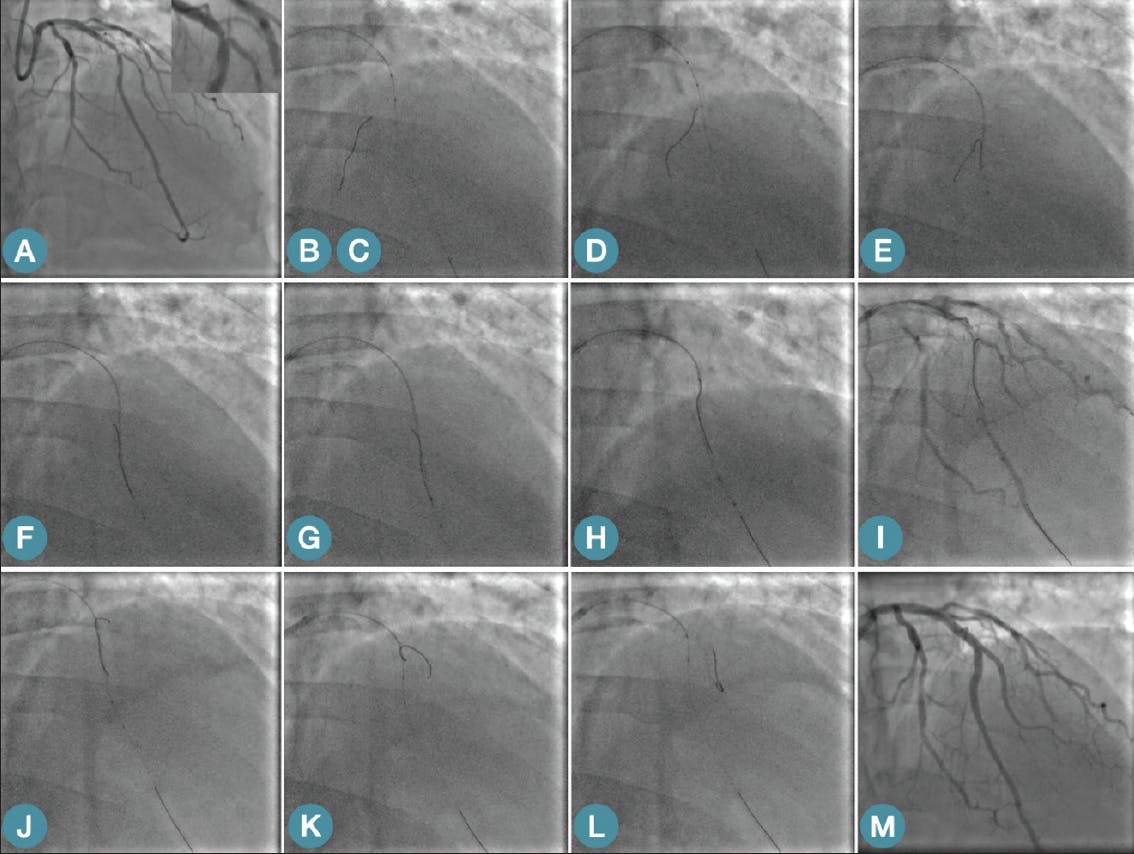

Figure 4. SRWT step-by-step in a LAD-diagonal bifurcation PCI. A LAD-diagonal bifurcation PCI with a difficult angulated side branch take off (A). A workhorse guidewire is inserted in the main branch, DLC advancement and wiring of a distal septal with a soft polymer jacketed wire (B, C). The DLC is firmly pushed distal to allow the wire to buckle and form the hairpin shape inside the coronary tree (D-G). The DLC and wire are pulled back gently as a unit to reach side branch (G, H). The hairpin wire is pulled back very gently and with minimal torque movements adjusted to engage and cross toward the distal side branch (H-L). Final result after IVUS-guided mini-crush stenting (M).